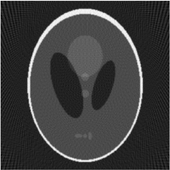

If a function represents an unknown density, then the Radon transform represents the projection data obtained as the output of a tomographic scan. Hence the inverse of the Radon transform can be used to reconstruct the original density from the projection data, and thus it forms the mathematical underpinning for tomographic reconstruction, also known as image reconstruction.

The process of reconstruction produces the image (or function in the previous section) from its projection data. Reconstruction is an inverse problem.